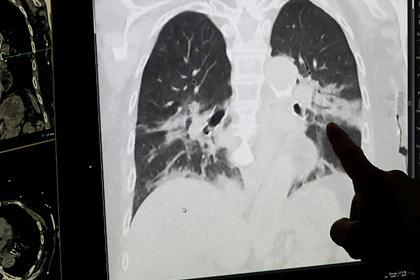

Иммунолог рассказал о поражении грибком легких пациентов с коронавирусом

Легкие пациентов с коронавирусом, помимо вирусной и бактериальной пневмоний, может поражать грибковая инфекция. Об этом в интервью «Известиям» рассказал заведующий кафедрой клинической микологии, аллергологии и иммунологии СЗГМУ имени Мечникова Николай Климко.

Во втором случае развивается грибковая пневмония, вызванная грибами рода Aspergillus. Фактор риска для ее появления — сама коронавирусная инфекция, так как она приводит к значительному нарушению местных и системных механизмов иммунной защиты. Кроме того, заражение грибком вызывают препараты глюкокортикостероиды и биологические иммуносупрессоры. Их применение сопровождается вынужденным снижением количества иммунологически активных клеток.

Климко заверил, что грибковая инфекция хорошо лечится, однако основная сложность заключается в том, что такое поражение часто не могут обнаружить вовремя. Так, пациентам с коронавирусом не проводят бронхоскопию, вероятно, из-за тяжести состояния пациентов.

В октябре патологоанатом описала состояние легких умерших пациентов с коронавирусом после вскрытия. По словам медика, орган значительно отекает и весит в несколько раз больше положенного. Смерть пациентов с коронавирусом зачастую наступает в результате тромбоэмболии — закупорки легочной артерии.